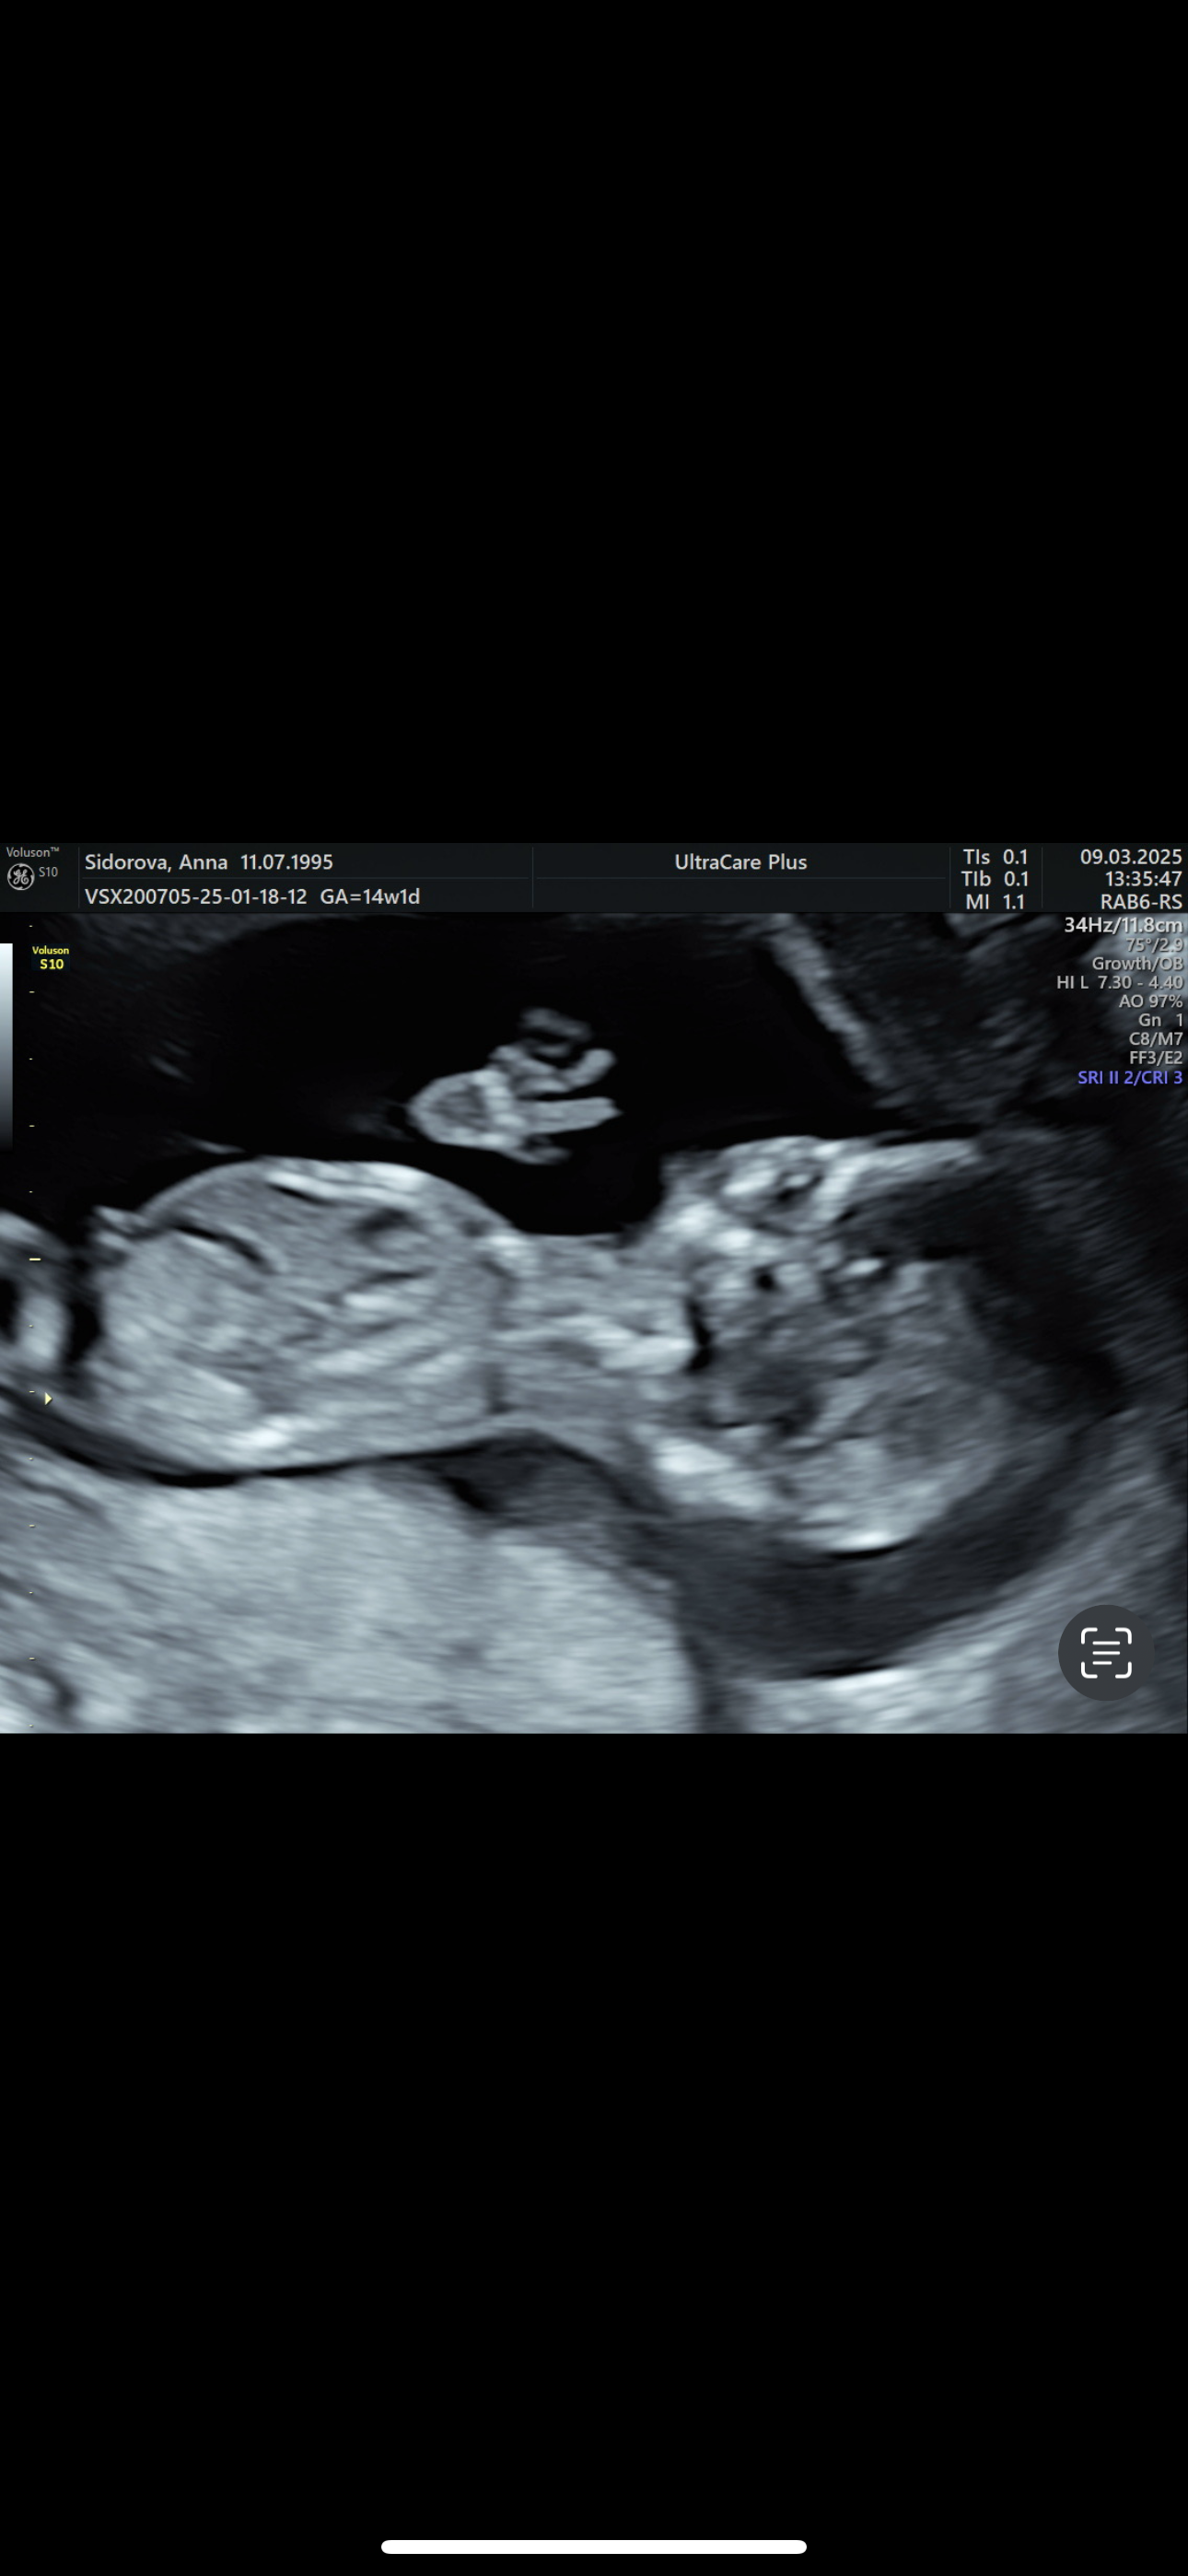

Пол малыша

Девочка, половой бугорок параллельно в телу. Ни на одном фото мальчиком не выглядит. Снизу на таком сроке неинформативно смотреть, только сбоку.

На третьей фотке с наклейкой-это вид снизу, со стороны попы? Если да, то это девочка. Хотя я бы гендер пати до 20ти недель делать не стала, не надежно это😬 мне до 20ти недель даже смотреть пол отказывались на узи, а в 20 там уже 100% точно можно определить

Скрининг в 13,5 недель в МедЭксперт. Пол двойни❤️💙